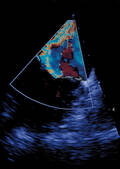

Künstliche Herzklappen: Fehlfunktionen vermeiden

Eine aktuelle retrospektive Studie legt Daten der kardialen Computertomografie mit der gegenwärtigen Standard-Untersuchungsmethode, dem Ultraschall, und dem Re-Operationsbefund übereinander, um Aussagen über Funktionsprobleme von...[mehr]